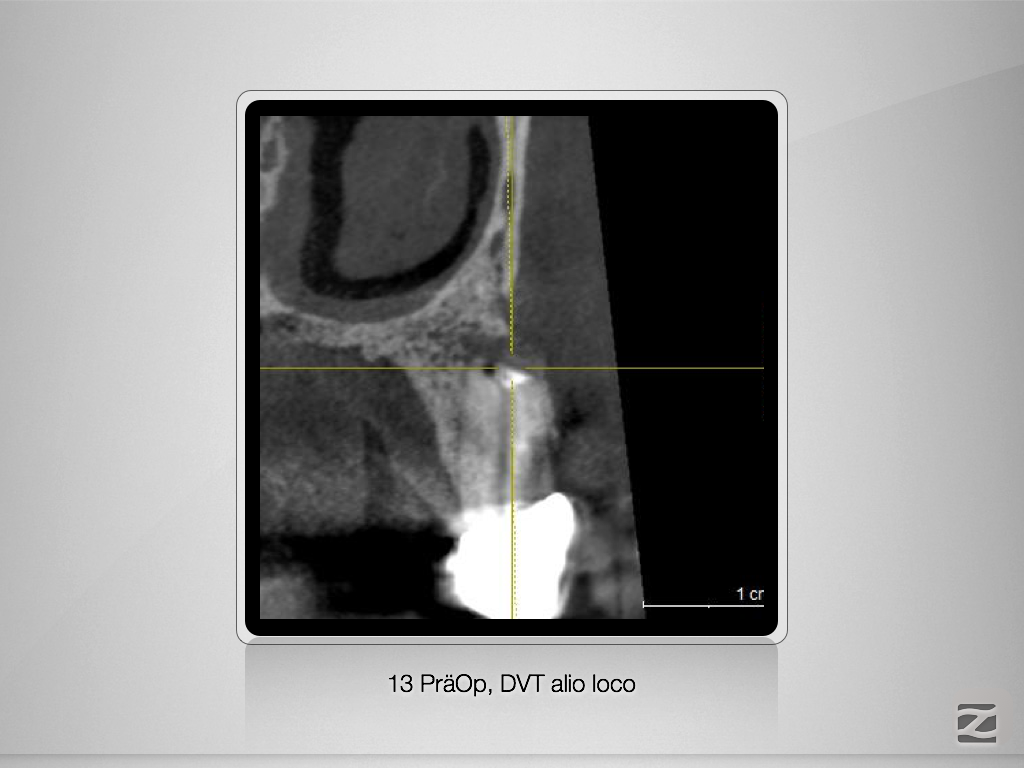

13D.003

Ketac Silver retrograd